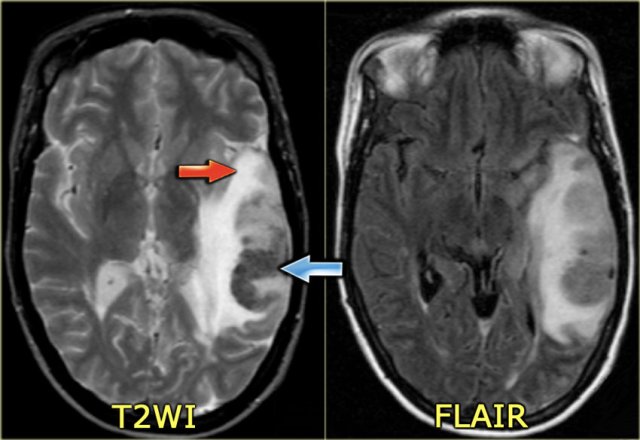

On the left a similar case on MR.

There is a combination of vasogenic edema (red arrow), cytotoxic edema and hemorrhage (blue arrow).

These findings and the location in the temporal lobe, should make you think of venous infarction due to thrombosis of the vein of Labbe.

The next examination should be a contrast enhanced MR or CT to prove the diagnosis.